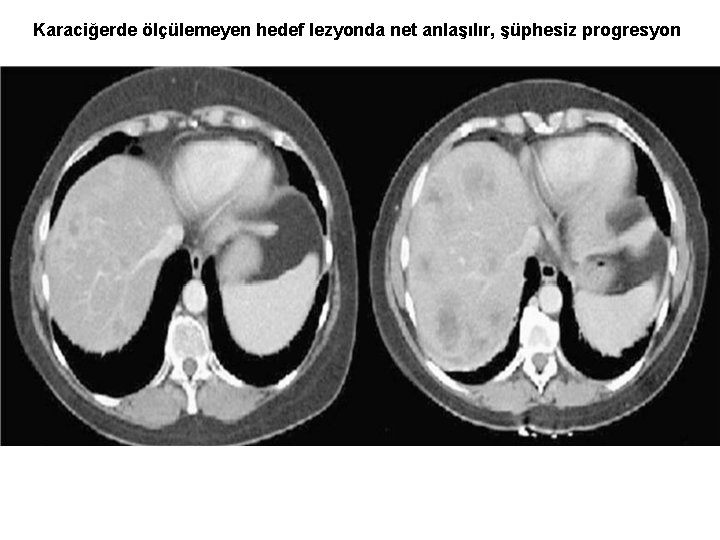

Cevap Kriterleri-Hedef Olmayan Lezyonlar • Progresif Hastalık: Şüphesiz şekilde varolan hedef olmayan lezyonlarda büyüme (Bir ya da daha fazla yeni lezyon çıkması ) • Hedef olmayan lezyonların birinde artış yeterli değil tümünde artış olmalı.

Karaciğerde ölçülemeyen hedef lezyonda net anlaşılır, şüphesiz progresyon